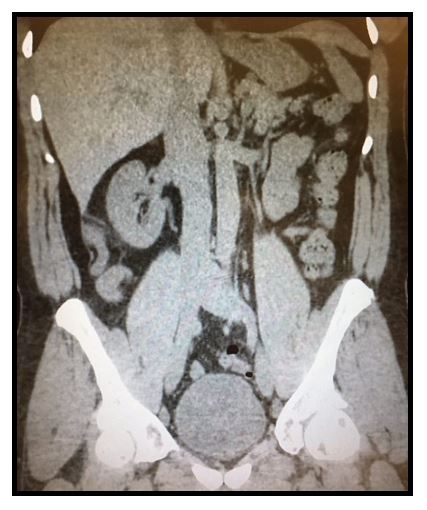

Abdominal CT

History. A 46-year-old man with no significant past medical history presents to the emergency department for 3 days of slowly progressive, constant, right-sided abdominal pain. He notes that the pain is worse with movement or coughing. He reports no nausea, vomiting fever, diarrhea, or other complaints.

Examination. Vital signs are normal except for a temperature of 99.2°F and respirations at 22 per minute. The abdomen is soft. The area of maximal pain indicated by the patient is also the area of maximal tenderness and is located midway between McBurney's and Murphy's points. There is no guarding or rebound. He also has mild right-sided costovertebral angle tenderness.

Initial Concerns: gallstone, kidney stone, appendicitis